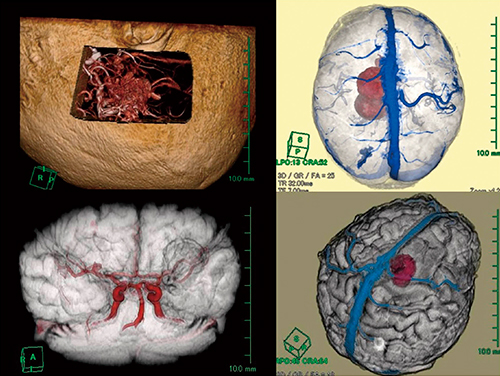

3.手術シミュレーション

主に脳腫瘍や脳動静脈奇形(AVM)の手術シミュレーション画像を作成している。撮像は造影FLASH法のみを用いて,複数のシーケンスを用いることによる位置ズレを避けている。この1つの元画像から頭表,頭蓋骨,脳表,腫瘍,血管を分離して配色した後,再構成してシネ表示で報告している(図3)。

図3 手術シミュレーションイメージ

頭表→脳表→手術部位や脳表からの透過像などをシネ表示で描出する。